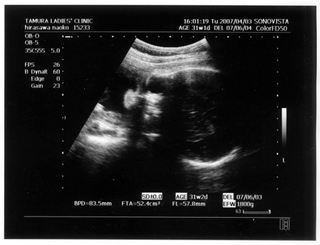

× [PR]上記の広告は3ヶ月以上新規記事投稿のないブログに表示されています。新しい記事を書く事で広告が消えます。 9ヶ月(32週と5日) 体重:2072g BPD(頭を上から見た耳から耳の幅のような感じ):84.6㎜ FTA(お腹の断面):60.8平方㎝ FL(大腿骨長 太ももの骨の長さ):61.2㎜ 9ヶ月(35週と2日) 体重:2583g BPD(頭を上から見た耳から耳の幅のような感じ):90.2㎜ FTA(お腹の断面):72.8平方㎝ FL(大腿骨長 太ももの骨の長さ):64.8㎜ 久しぶりの記事アップです ![]() なんだかあっという間にGW終わってしましましたね~ ![]() きのうは雨のせいでだらけてしまって、記事書く予定ができませんでした ![]() ダンナっちには『雨降って ナオコ 動かず』といわれています・・・ ![]() さてさて、5月2日(35週と2日)の内診では、 子宮口が1センチ開いてきてることが発覚 先生に「もう少し入れておいてよ 張ったら休まなきゃダメ」と言われ、 薬 まで出されました。子宮の筋緊張状態をやわらげて、早産を防止 するんだそうです。 「慣れるまでは心臓がドキドキしたり、 手が震えたりしますけど、大丈夫ですから」 と先生から説明を受けて、家で飲んでみると、 ほんとにドキドキ して、手もピクピク してきて、なんかラリった妊婦状態で不思議でした。 今週に入って、だいぶ慣れたようでそんなにラリっては いないけど、飲んでから1時間くらいは運転を控えています ![]() ベイビー自体は2500gをすでに超えて、動きも活発で元気にしています ![]() 1センチ開いてもなかなか進まないこともあるし、どうなるかはわかりません ![]() でも、ベイビーがお腹から出てきて自分で呼吸をするために、 必要な肺のサーファクタント(界面活性物質)の分泌は、妊娠33~36週ころから になります。 哺乳反射といって、ベイビーがおっぱいを飲むための反射的に吸い付く能力は 32~34週で完成するそうです。 網膜の血管が完成するのは35週前後だそうです。 つまり、わたしは今週臨月(36週)に入りましたが、 やっぱり正期産である37週からの出産が望ましいみたいです ![]() ![]() 医療も発達してきてるし、 ほぼ完成しているので生きられないことはぜんぜん無いんですけど、 十分に成長して「時」が満ちて生まれるのが一番みたいですね~ ![]() 「はやく会いたいけど、あと3週間くらいお腹の中にいてね~」 とベイビーに言っています ![]() 薬をもらってから、「張り」を意識するようになったんですけど、 けっこう張るんですよね~ 張るとなんとも動きづらい ![]() パンパンで重みのある厚手のゴムボール を持って歩くような・・・そして、 膀胱圧迫![]() ![]() ![]() トイレ行くにも駆け込む動作がつらい 歩けない![]() 、走れない![]() ![]() 悲惨な結末 ![]() ![]() ![]() ![]() を迎えまいとして、キュッと閉める運動をせざるをえなくなります・・・ ![]() PR